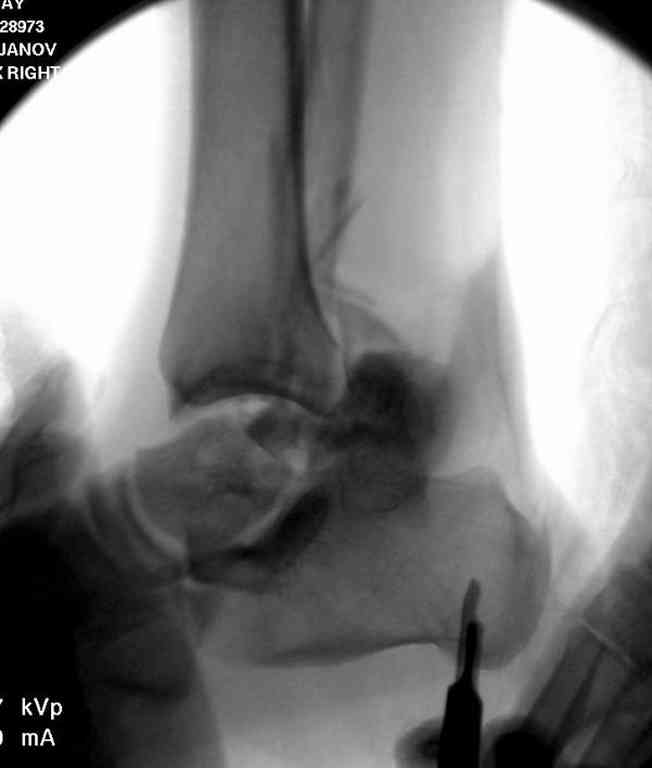

Здесь на фото примеры:

Переломовывих тарана с повреждением медиальной стороны. Через 4 часа после поступления проведена репозиция и фиксация тарана после Irrigation&Debridment. Частичное несращение медиальной лодыжки не беспокоит, вернулся к активному образу жизни. Полная нагрузка разрешена через 11 недель. Финальные снимки через 11 месяцев.